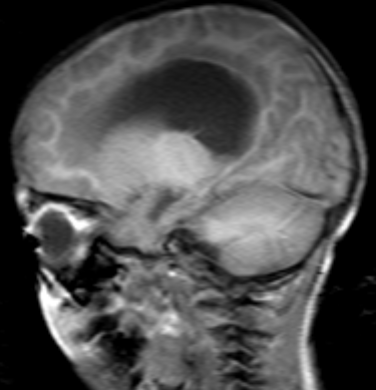

• 左额叶肿瘤切除术后案例【左额叶肿瘤】7岁左额叶肿瘤切除

左额叶肿瘤切除术后案例【左额叶肿瘤】7岁左额叶肿瘤切除

内容简介: 患者档案:性别:男就诊年龄:7岁(当时)病名:左额叶肿瘤切除术后病理诊断:伴 BCOR 内部串联重复的中枢神经系统肿瘤就诊国家:日本就

详细资料 左额叶肿瘤切除术后案例【左额叶肿瘤】7岁左额叶肿瘤切除